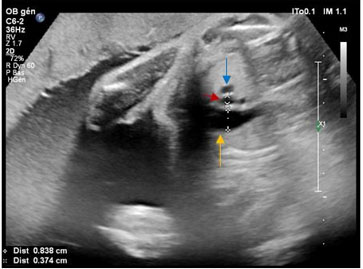

A 55-year-old male, not known to have any medical background, was admitted in secondary hospital with history of sudden onset of lower back pain, which is more in the left side, radiating to bilateral lower limbs and aggravated by movement. Back pain followed by onset of high-grade fever and malaise. No history of trauma, respiratory symptoms, neurological deficit, or urinary symptoms. Physical examination was significant for left lumbar tenderness, positive straight leg raise test (SLR), and temperature of 38°C. Laboratory tests showed C-reactive protein (CRP) of 246 mg/L, white blood count (WBC) was (7.5×109/L), and plasma glucose level was 14 mmol/L. In further investigation during admission glycated hemoglobin (HbA1C) came as 8%. Lumbosacral X-ray was not significant. Computed tomography (CT) abdomen-pelvis with intravenous (IV) contrast was done and it was normal apart from mild spondylo-degenerative changes. Blood culture came positive for Methicillin-resistant Staphylococcus aureus (MRSA). Furthermore, MRI with and without gadolinium contrast was requested and showed widening of the left facet joint at L3/L4 level with moderate effusion, eroded articular surface, and joint effusion (Figure 1). The L4 left lamina showed edematous bone marrow with thickened related intraspinal left posterolateral epidural soft tissue forming 10 mm thickness phlegmon which extend into left neural foramen and inferiorly up to L5/S1 level (Figure 2). The adjacent paraspinal muscle showed phlegmon with increased signal intensity in T2 Short Tau Inversion Recovery (STIR) (Figure 3). There was increased enhancement at T1 post-contrast images at the level of the articular surface of L3/L4, adjacent paraspinal soft tissue with evidence of bone marrow edema of the lamina (Figure 4).

Figure 1: Axial T2-weighted lumbosacral MRI without contrast at L3/L4 level shows widening of left facet joint (arrow) with moderate effusion and eroded articular surfaces.